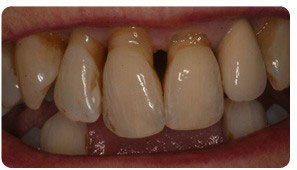

Periodontal (Gum) disease describes swelling, soreness or infection of the tissues supporting the teeth. There are two main forms of gum disease: gingivitis and periodontal disease. Nearly all gum disease is caused by plaque. Plaque is a film of bacteria which forms on the surface of the teeth and gums every day. Many of the bacteria in plaque are completely harmless, some and in particular one has been shown to cause gum disease.

- Periodontal disease – long-standing gingivitis can turn into periodontal disease. There are a number of types of periodontal disease and they all affect the tissues supporting the teeth. As the disease gets worse the bone anchoring the teeth in the jaw is lost making the teeth loose. If you don’t treat it, the teeth may eventually fall out.

- Gums that have receded

Please note that we didn’t enhanced this photo and we are using it with the patient’s permission.